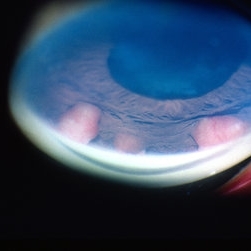

HLA-B27 Associated Uveitis

Jun 4 2014 by Henry J. Kaplan, MD

Severe anterior uveitis with fibrinous reaction and hypopyon formation related to HLA-B27. Notice the membrane on the lens surface.

Condition/keywords: acute anterior uveitis, HLA-B27, hypopyon